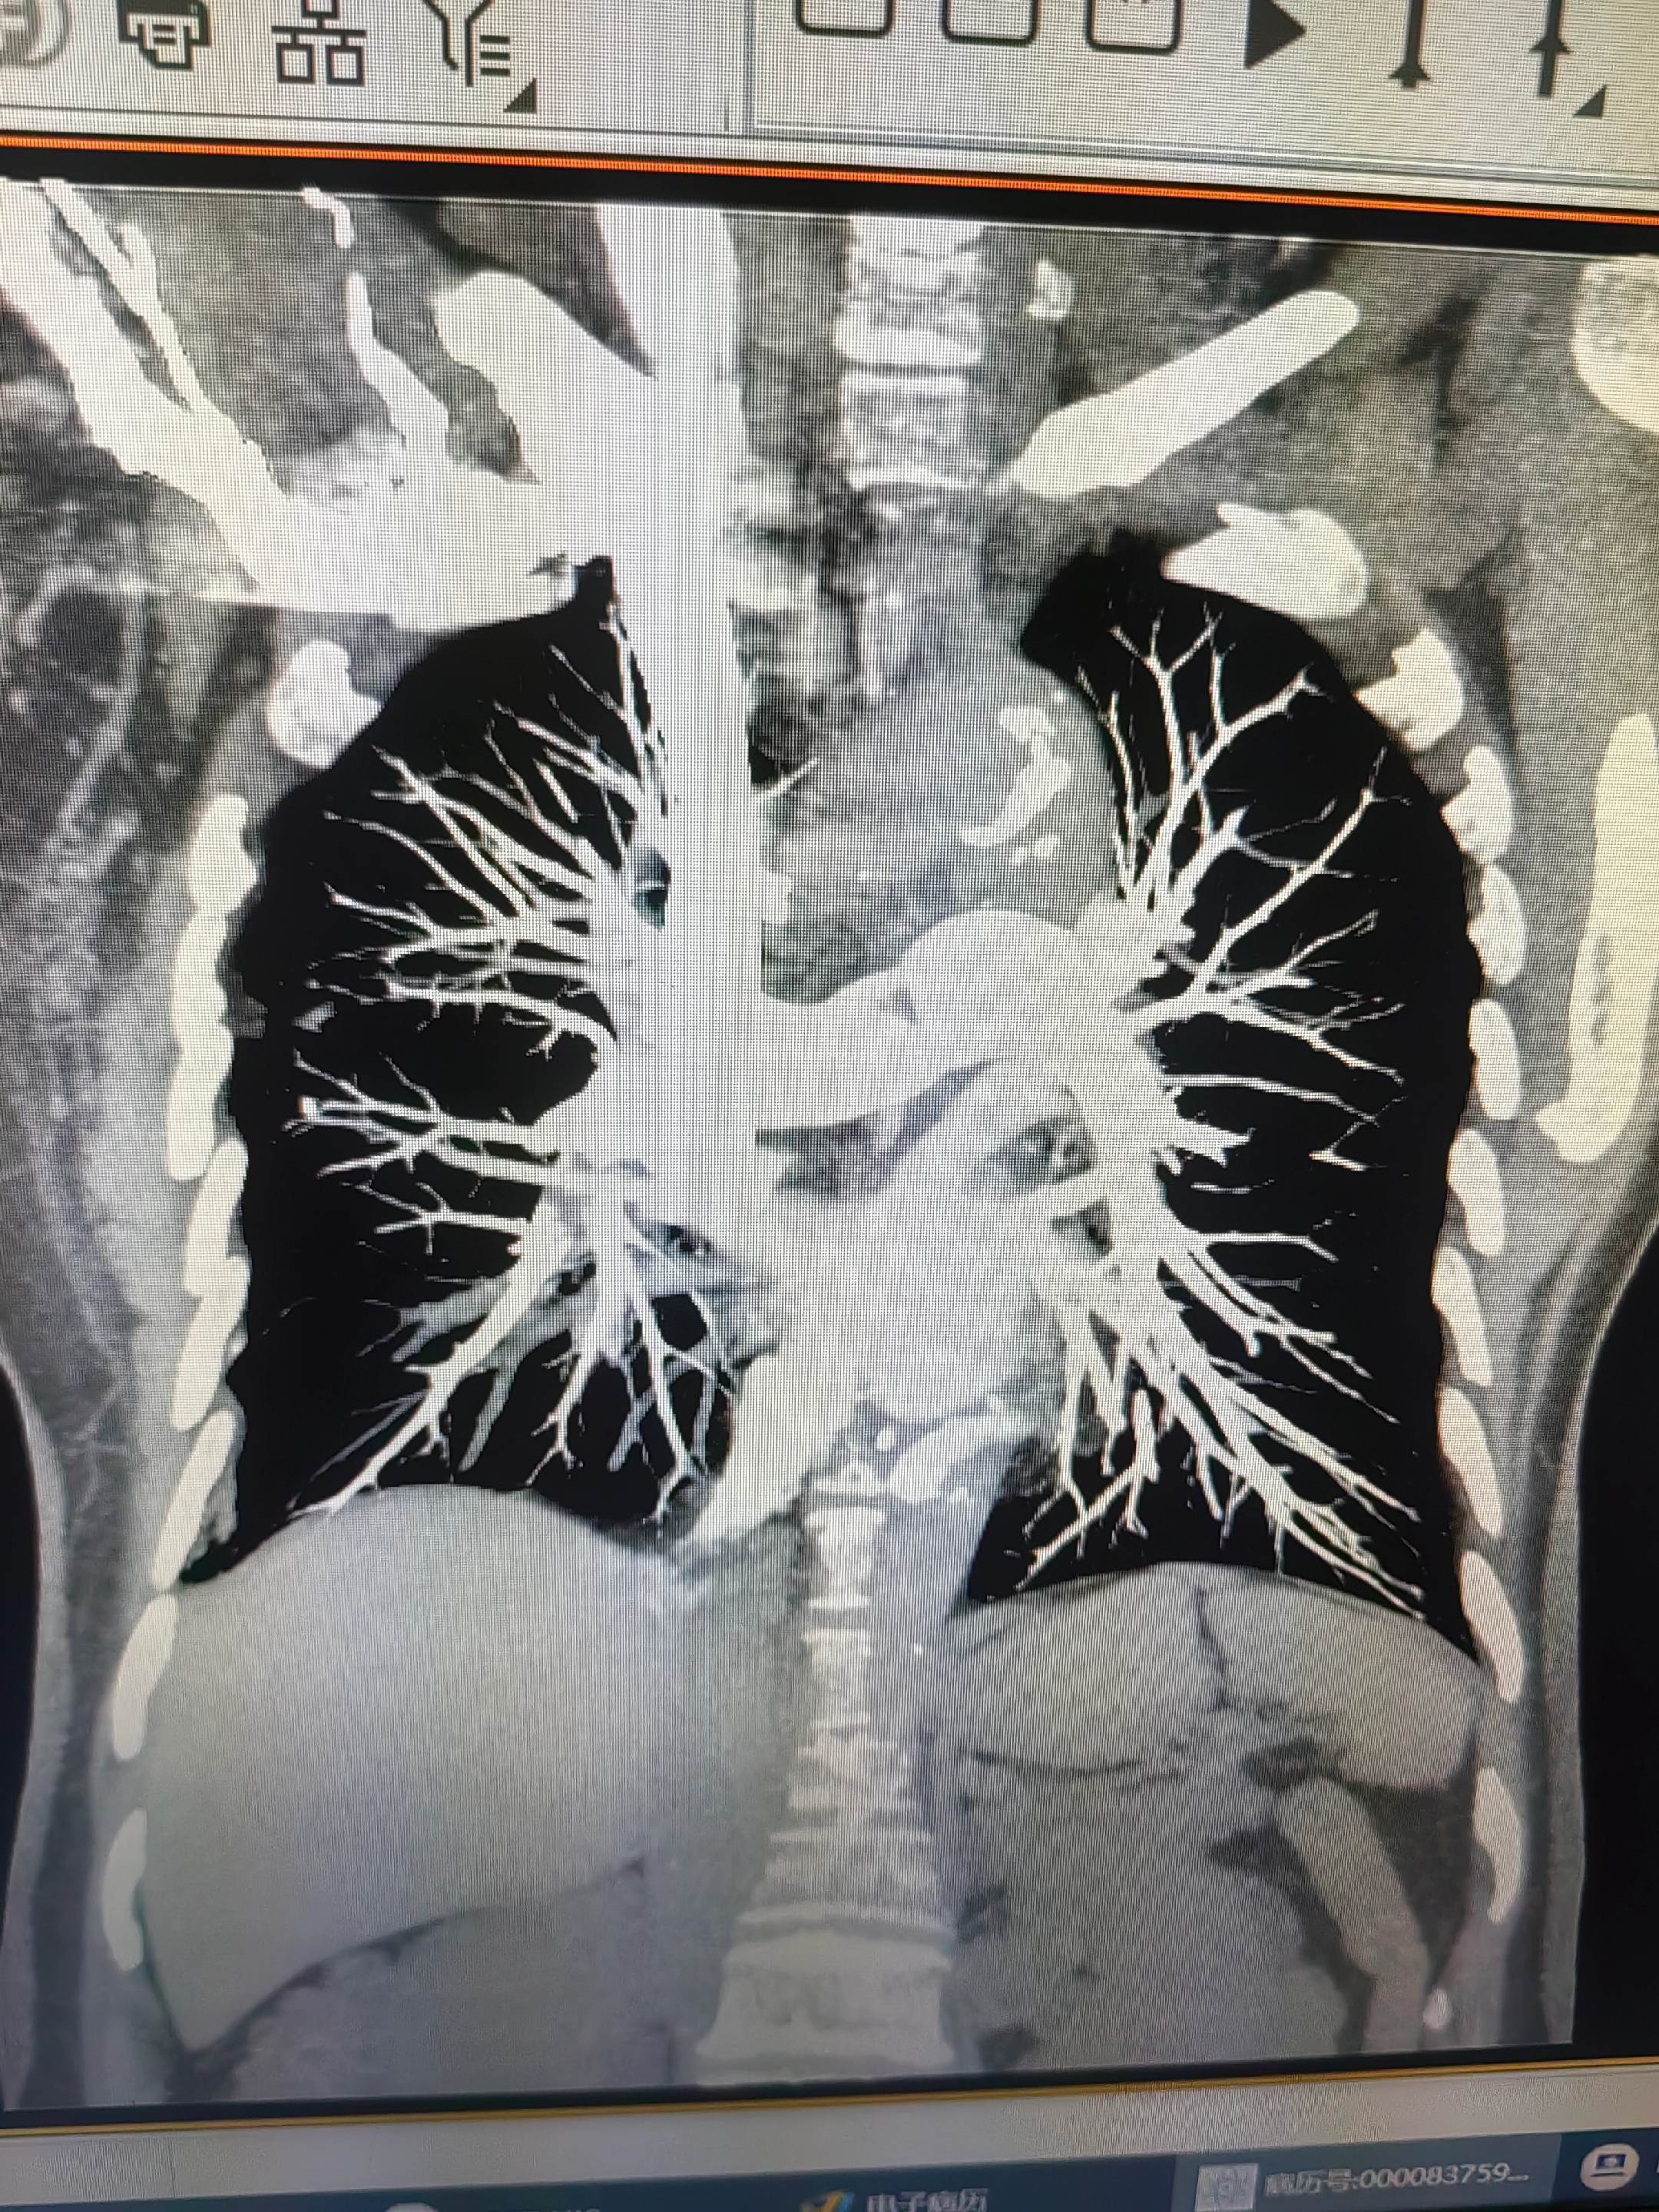

肺栓塞。